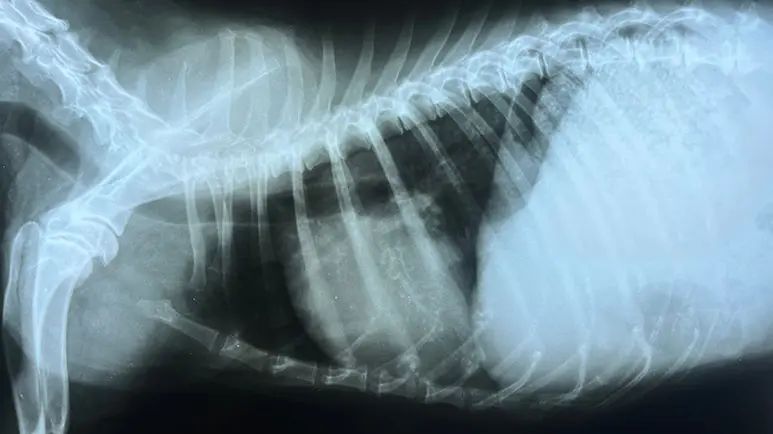

- Chest x-rays — X-rays of your dog’s chest can give important information about her heart and lungs. The heart’s size, shape and position can be visualized, as can blood vessels and lung patterns.